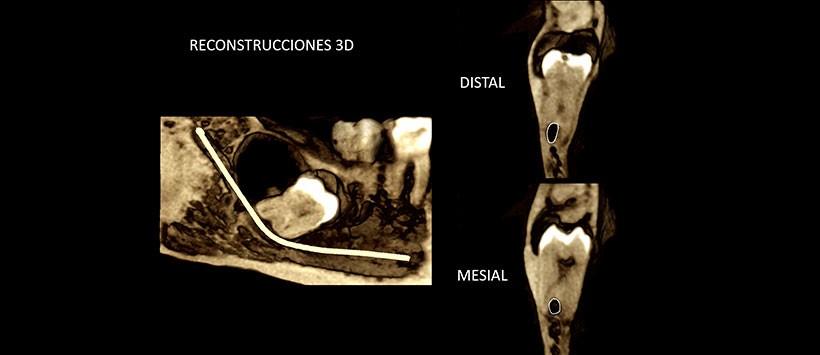

A la evaluación de la tomografía computarizada de haz cónico (CBCT), mediante reformación panorámica (Figura 1), cortes transaxiales (Figuras 2) y cortes tangenciales (Figura 3), se aprecia la impactación de la pieza 4.8 en posición horizontal, con presencia de una de una imagen hipodensa en relación a la corona de dicha pieza, de limites definidos, corticalizados, que ocasiona leve expansión y adelgazamiento de la tabla ósea lingual.

Así mismo, al evaluar la relación de la pieza impactada con el conducto dentario inferior se observa una estrecha relación entre ambas, encontrándose este último discurriendo por el medio de ambas raíces.

En las reconstrucciones 3D se observa claramente las imágenes antes descritas y su relación con estructuras adyacentes. (Figuras 4, 5 y 6)